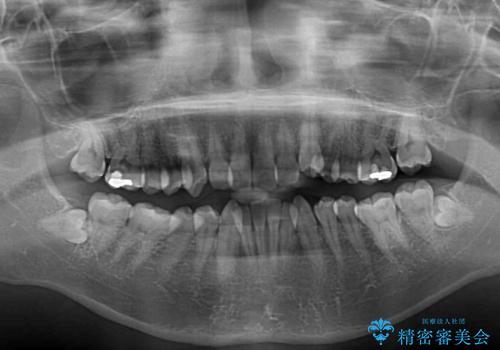

- 上下前歯のデコボコと八重歯を気にして来院された患者様です。

叢生を解消する際に出っ歯とならないようにするために、上下左右の小臼歯計4本を抜歯することとしました。

奥歯の咬み合わせが理想的であり、歯の移動に時間のかかる出っ歯でもなかったため、2年程度で治療を終えることを目標としましたが、無事に予定通りの2年間で終えることができました。